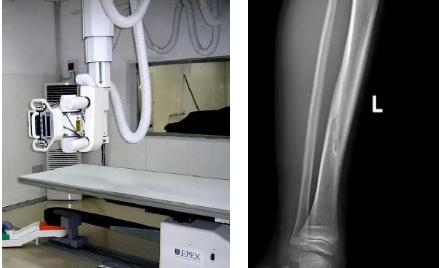

1.定期復(fù)查。一般于骨折后2-4周,骨折進(jìn)入骨痂期,骨折斷端有新生骨形成,呈明顯高密度,無論是X線或是CT,都能比較清晰觀察到,通過前后圖像對(duì)比,較容易診斷隱匿性骨折。

2.CT或MRI檢查。CT是斷面成像,不會(huì)出現(xiàn)重疊而導(dǎo)致漏診,同時(shí)CT還可以進(jìn)行多平面的重建,除了發(fā)現(xiàn)X線無法發(fā)現(xiàn)的骨折外,還可以三維直觀的顯示骨折的程度,對(duì)臨床治療有指導(dǎo)意義。CT無法發(fā)現(xiàn)骨裂、不全骨折或者骨挫傷,對(duì)軟組織的損傷診斷也有局限性,MRI就可以發(fā)現(xiàn)這些損傷。